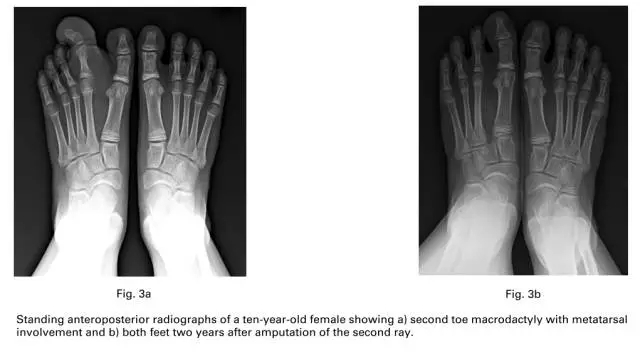

通过这些标准后,研究内包括16名患者18只足,7名男性,9名女性。平均手术年龄在46个月,6例是右足,8例是左足,2例是双足都有。巨趾影响一个足趾的是3例,2个足趾是10例,3个足趾是五例。

很多的作者报道放射状切除就可以减小前足的宽度而不需要额外的手术干预。尽管骨骼发育成熟后跖列切除的效果没有被报道,但是有报道了2例患者7年的随访后有正常的步态和穿鞋子。